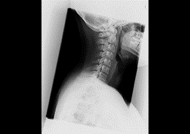

胸部、腹部をはじめ、頭部、椎体(頚椎・胸椎・腰椎)、骨盤、四肢など、全身の骨の撮影を行います。X線を用いて痛みを感じることなく、体の中の様子を調べることができる検査です。病変や骨折などを診断しやすくするため、いろいろな体位、方向から撮影します。 読影(画像診断)は日本放射線学会で認定されている経験豊富な放射線専門医が担当しています。

| 頸椎 | 腰椎 |